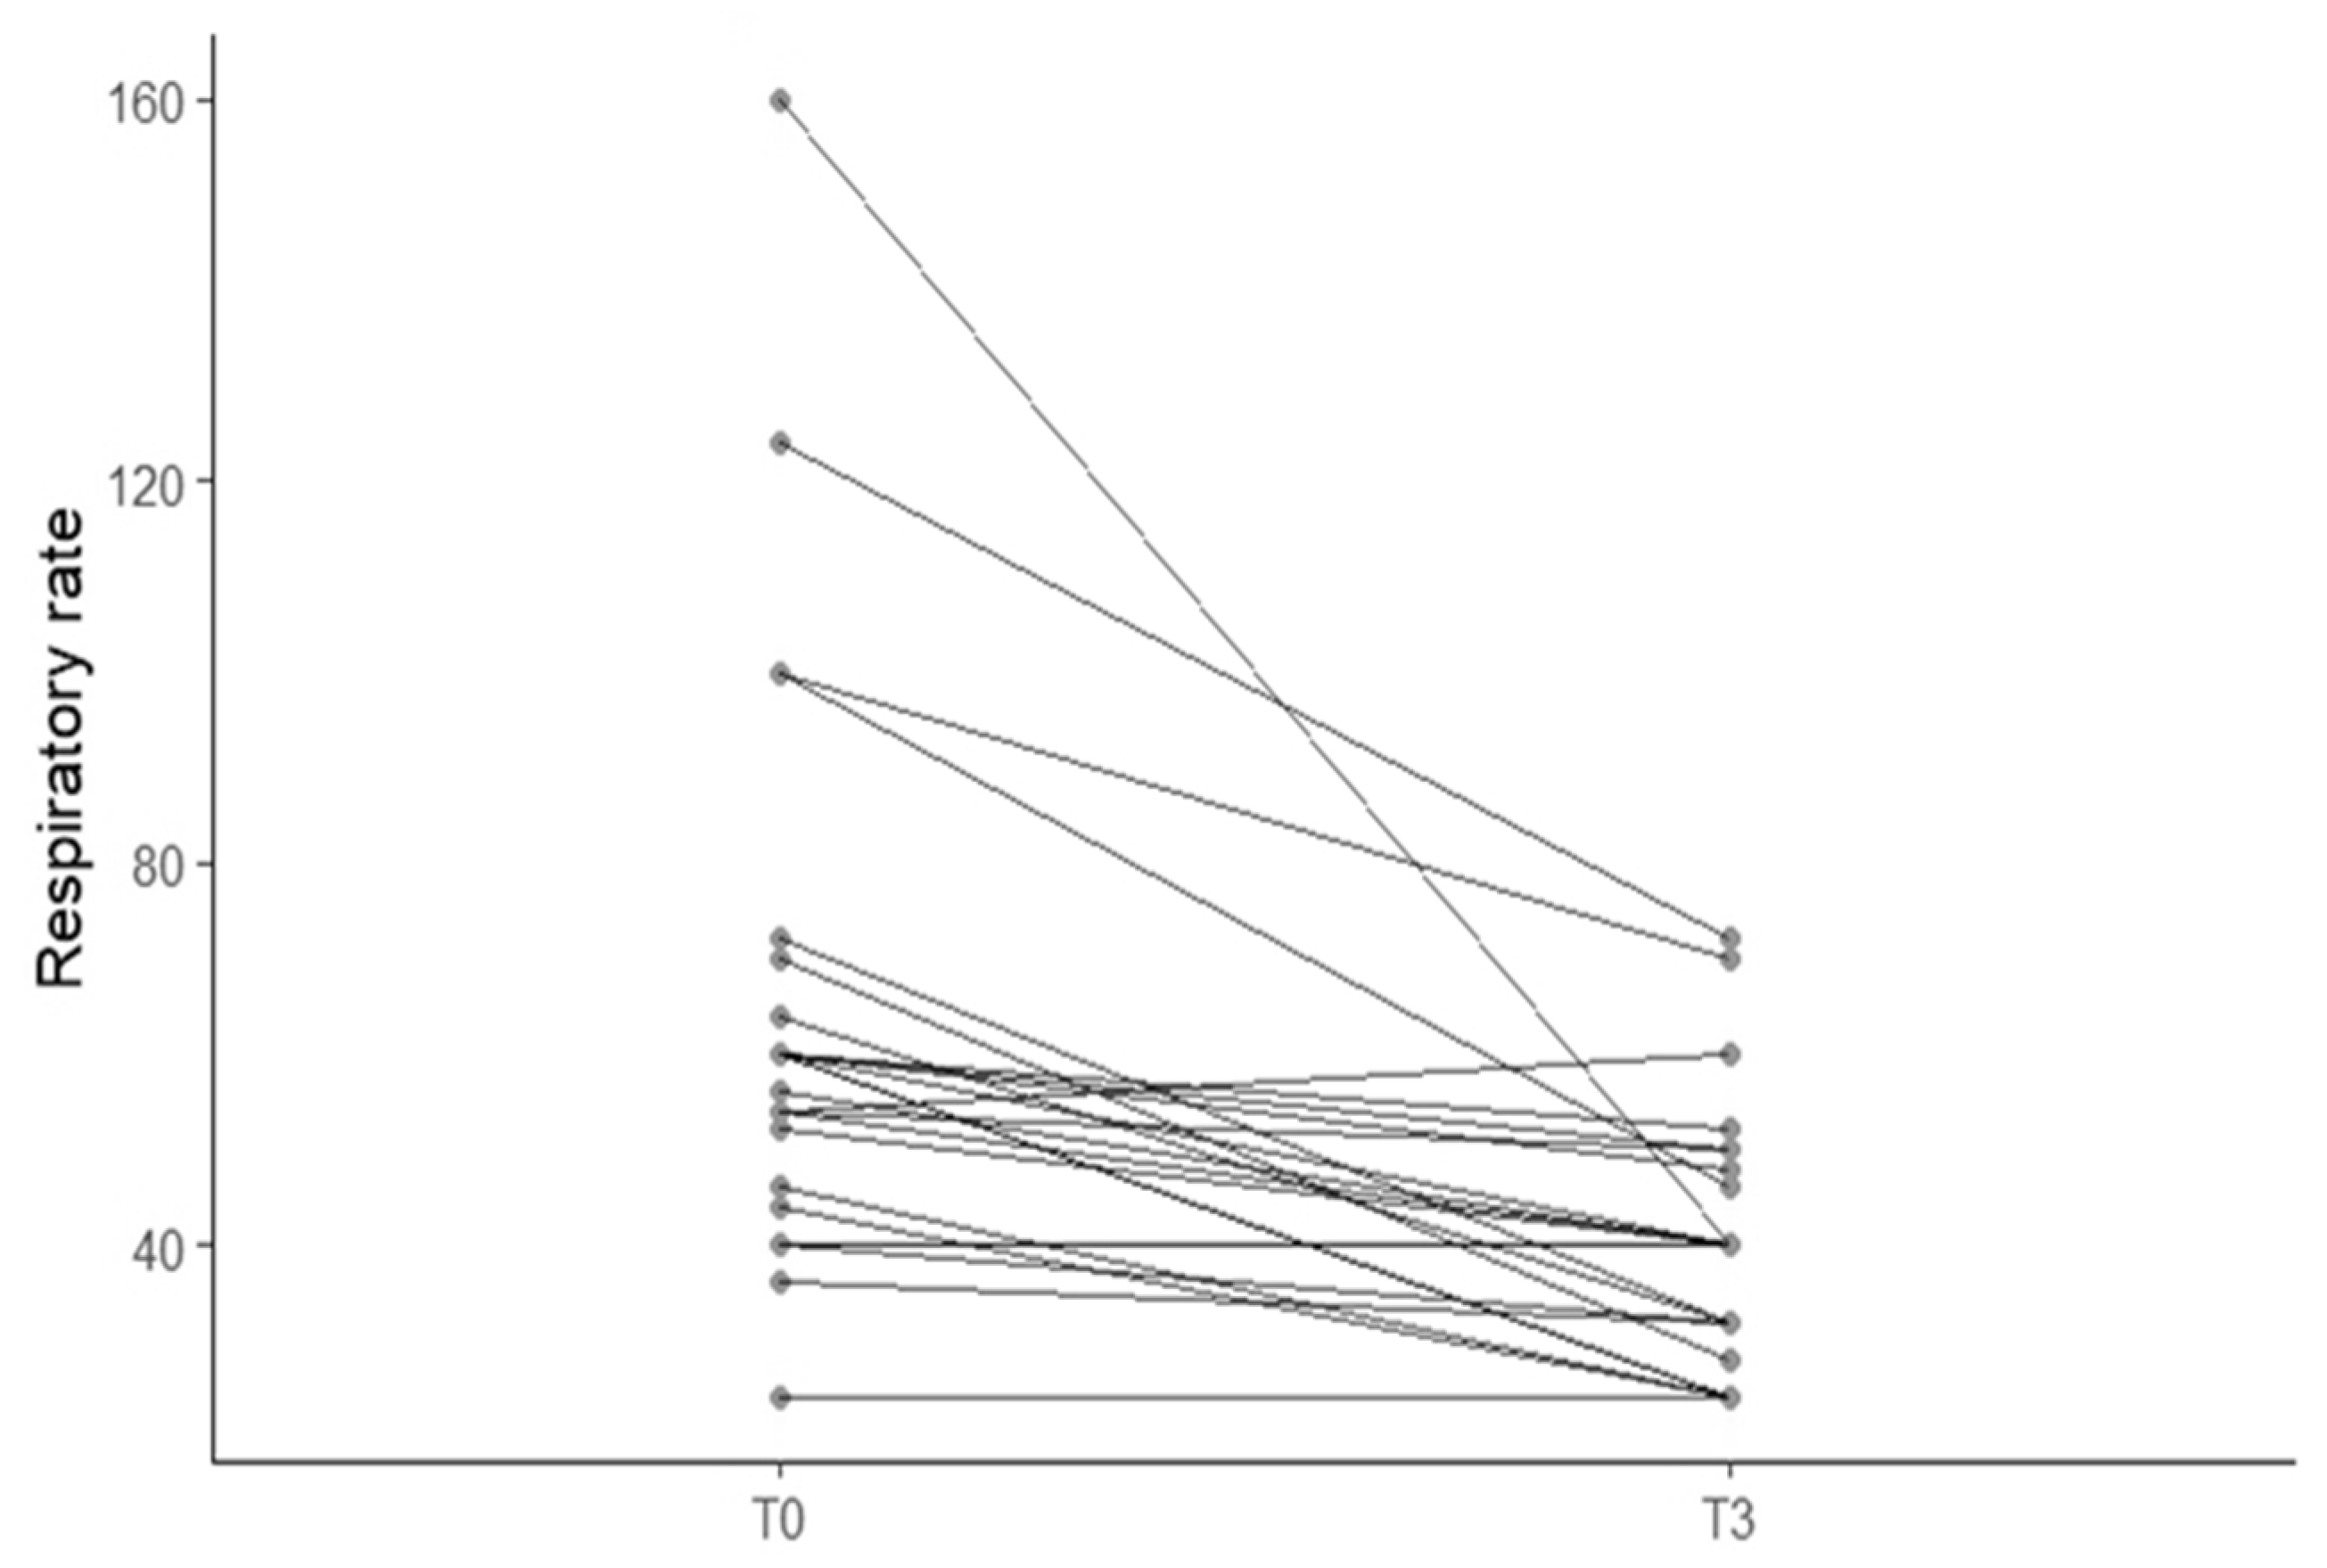

3.2. Correlation Between Furosemide Dose, Breathing Improvement and Left Atrial Size